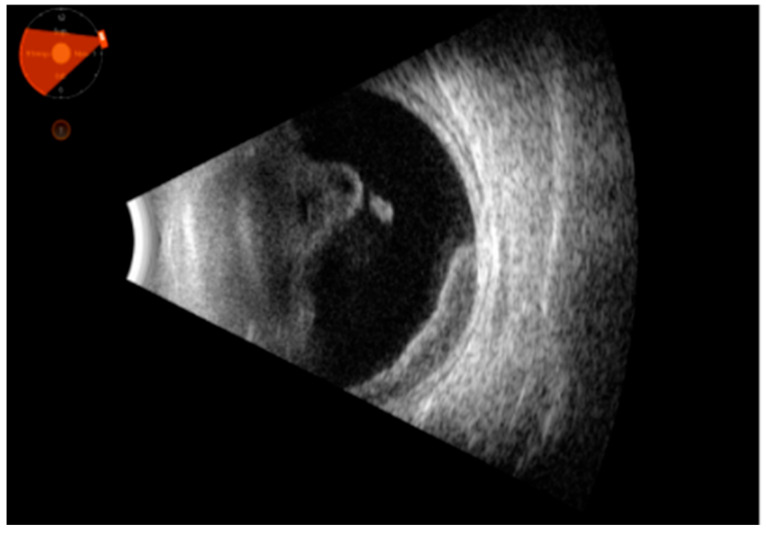

背景和目的:葡萄膜炎掩盖综合征或假面综合征(UMSs)是一组眼部疾病,有几种系统性的潜在原因,恶性或非恶性,模仿葡萄膜的炎症状态。它们通常难以用眼科检查等传统技术检测和诊断。眼部B(二维)超声(OBU)是一种无创、可重复、快速的超声方法,对导致全身性疾病的间接征象有效。其有效性与其他成像工具相当。多发性硬化的病因往往很严重,因此早期诊断和及时治疗至关重要。本研究旨在确定这些形式的超声征象,这可以帮助医生发现潜在的UMS原因。材料和方法:这是一项连续、回顾性、非随机的研究。该研究于2022年1月至2024年12月在意大利巴里大学医院综合诊所进行。共纳入186例患者,年龄从10岁到85岁不等。所有患者均行b超检查(Quantel Medical ABSolu Ocular Ultrasound)。结果:所有患者均报告视力模糊,并伴有视力下降(结论:准确诊断UMS相当具有挑战性,许多不同类型的UMS经常未被发现。这种识别的复杂性往往导致诊断不足,这意味着提高对这种疾病的认识和理解是必不可少的,以便更好地识别和治疗。及早发现这些形式是必要的。OBU的使用可以帮助早期诊断这些形式的间接迹象并及时治疗。它与其他诊断成像技术(如核磁共振成像)相比要好,但这并不意味着它取代了它们;它可以为多模态成像提供附加价值。

Background and Objectives: Uveitis-masked syndromes or masquerade syndromes (UMSs) are a group of ocular conditions with several systemic underlying causes, malignant or nonmalignant, that mimic the inflammatory status of the uvea. They are often difficult to detect and diagnose with traditional techniques, such as ophthalmic exams. Ocular B (bidimensional)-ultrasound (OBU) is a non-invasive, repeatable, rapid ultrasound method effective in indirect signs that lead back to systemic diseases. It is comparable in effectiveness with other imaging tools. The cause of UMSs can often be serious, and therefore early diagnosis and prompt treatment are critical. This study aimed to identify the sonographic signs of these forms, which can help physicians discover the cause underlying UMS. Materials and Methods: This was a consecutive, retrospective, nonrandomized study. This study was conducted at the University Hospital Polyclinic of Bari, Italy, from January 2022 to December 2024. A total of 186 patients were included, from 10 to 85 years old. They all underwent B-scan ultrasonography (Quantel Medical ABSolu Ocular Ultrasound). Results: All patients reported blurred vision, which could be accompanied by visual reduction (<20/40, Snellen charts), photophobia, floaters, flashes, proptosis, and redness. In all cases, we noted peculiar ultrasonographic signs, which allowed us to discriminate the underlying systemic diagnosis, such as vitreous corpuscles, choroid thickening, and primitive or metastatic solid tumors. Finally, we identified different diseases, such as primary intraocular lymphoma (PIOL), other lymphoproliferative conditions, orbital plasmacytoma, uveal melanoma, metastasis, endogenous endophthalmitis, retinal detachment, central serous retinopathy, metallic foreign bodies, ocular amyloidosis, and drug-induced UMSs. The sensitivity and specificity of ocular ultrasound compared to multimodal ocular imaging in UMSs were as follows: for primary intraocular lymphoma (PIOL) and other lymphoproliferative conditions, 0.98 (95% CI, 0.80-1) and 0.68 (90% CI, 0.40-0.92), respectively; for orbital plasmacytoma, 0.64 (92% CI, 0.52-0.86) and 0.66 (93% CI, 0.48-0.89), respectively; uveal melanoma, 1.00 (98% CI, 0.88-1.00) and 0.98 (95% CI, 0.86-0.98), respectively; metastasis, 0.75 (95% CI, 0.53-0.85) and 0.85 (95% CI, 0.48-0.98), respectively; endogenous endophthalmitis, 1.00 (95% CI, 0.50-1.00) and 0.83 (95% CI, 0.48-0.98), respectively; retinal detachment, both were 1.00 (95% CI, 0.87-1.00 and 0.84-0.97, respectively); central serous retinopathy, 0.60 (80% CI, 0.41-0.88) and 0.85 (95% CI, 0.52-0.98), respectively; metallic foreign bodies, 1.00 (95% CI, 0.78-1.00) and 0.99 (95% CI, 0.99-1.00), respectively; ocular amyloidosis, 0.77 (82% CI, 0.52-0.90) and 0.83 (80% CI, 0.49-0.88), respectively; and drug-induced UMSs, 0.64 (95% CI, 0.49-0.88) and 0.85 (95% CI, 0.52-0.98), respectively. Conclusions: Diagnosing UMS accurately can be quite challenging, and many of its different types frequently go undetected. This complexity in identification often leads to underdiagnosis, meaning it is essential to improve awareness and understanding of the condition in order to achieve better recognition and treatment. Early detection of these forms is imperative. The use of OBU can help diagnose indirect signs of these forms early and treat them promptly. It compares well with other diagnostic imaging techniques, such as MRI, but this does not mean that it replaces them; it can offer added value in multimodal imaging.